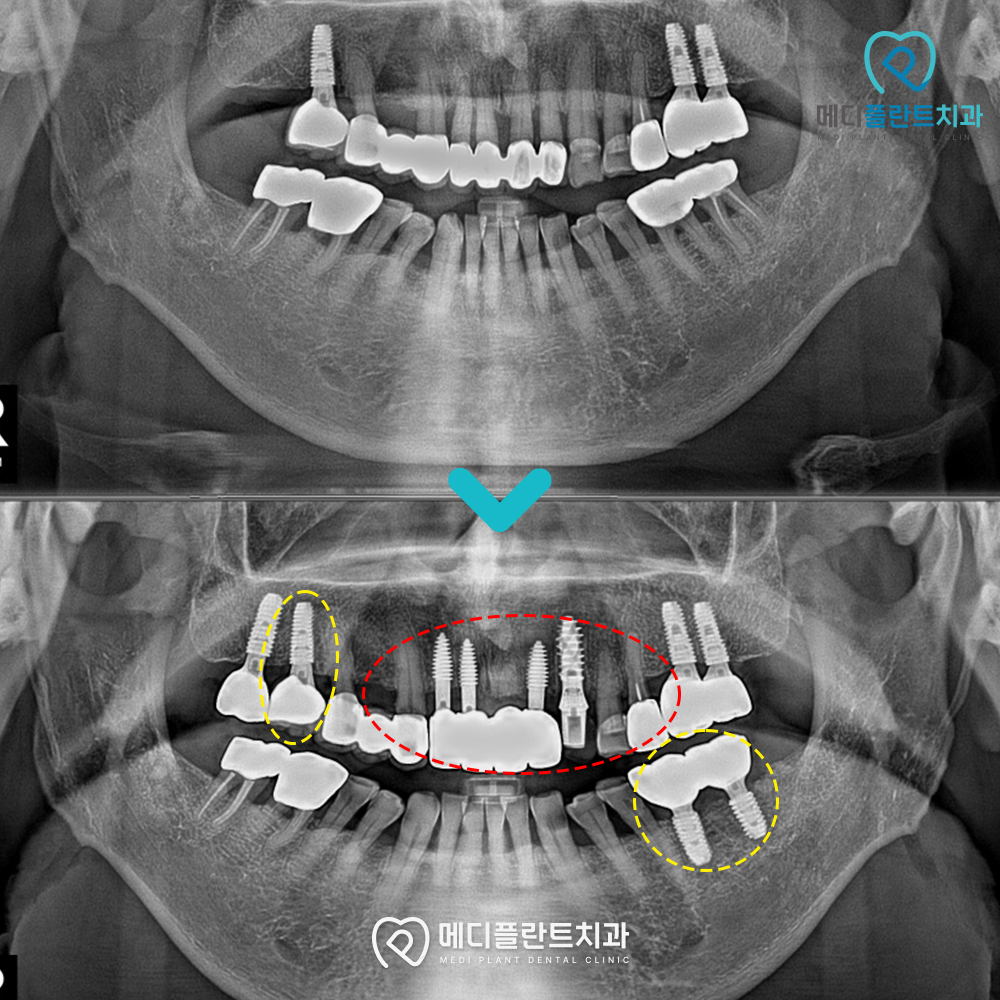

환자분께서는 오래된 앞니 보철물로 인해

심미적인 부분과 기능적인 부분 모두에서

불편함을 느끼고 계셨습니다.

초기 내원 당시에는 기존 보철물의 상태가

안정적이지 않은 모습이었으며,

이로 인해 저작 기능이 원활하게 이루어지지 않아

식사 시 불편감을 호소하셨습니다.

이에 따라 전체적인 교합과 기능을

함께 고려한 방향으로 치료 계획을 수립했습니다.

이번 증례에서는

상악 전치부를 중심으로 임플란트를 식립하여

지지 구조를 형성한 뒤,

기존 치아 및 보철물과의 조화를 고려해

보철을 연결하는 방식으로 진행했습니다.

.

또한 양측 구치부 역시

저작 시 힘이 고르게 전달될 수 있도록

추가적인 임플란트를 식립해

전체적인 균형을 맞추었습니다.

치료 후에는 전반적인 교합이

보다 안정된 상태로 자리 잡았으며

식사 시 느끼던 불편감도

줄어든 모습을 확인할 수 있었습니다.